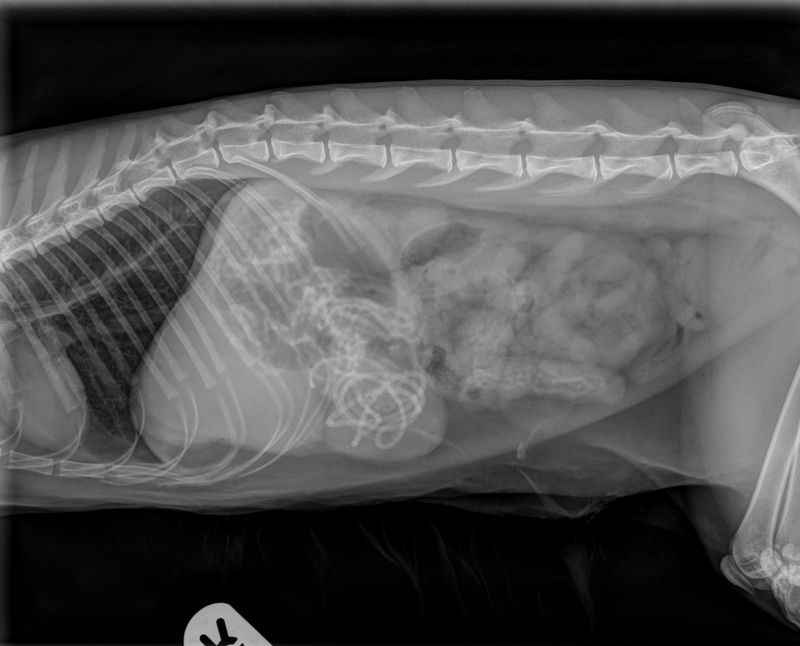

hile their antics can be entertaining, they sometimes lead to dangerous situations—especially when everyday household items become accidental chew toys or snacks. Veterinarians frequently rely on X-rays to uncover the surprising, and sometimes alarming, objects hidden in a cat’s digestive system.

Many of the items that show up in feline X-rays are things we would never expect a pet to swallow. From sparkly decorations to seemingly harmless strings, these everyday objects can cause serious health risks, ranging from digestive blockages to internal injuries. What makes it even more concerning is that cats often don’t show immediate signs of distress, so by the time symptoms appear, the problem could already be severe.

To help protect your furry friend, here’s a list of 14 common household objects that have been found in cats through X-rays. These are more than just stories—they’re real reminders that a little prevention can go a long way. Whether you’re a new cat parent or a seasoned feline fan, being aware of these dangers is essential to keeping your companion safe and healthy.